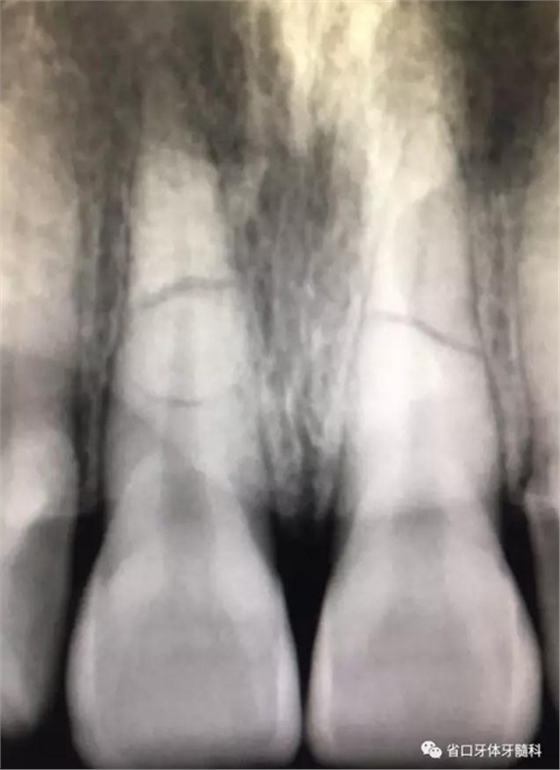

X線片:11、21根中段見橫行根折線,無移位,根尖無明顯異常。

圖2 術(shù)前根尖片